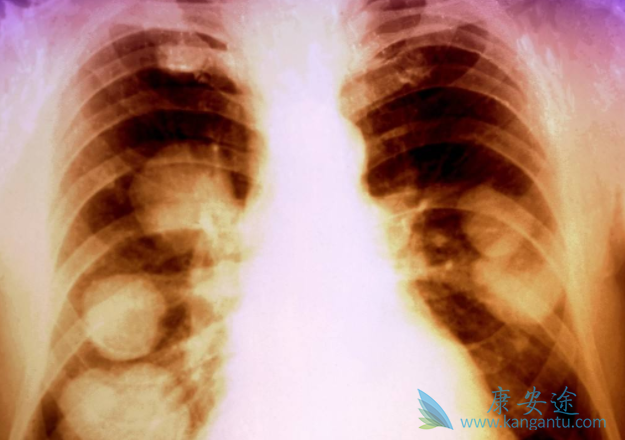

在肺癌的治疗过程中,对于又有相应突变药物的患者,医生多建议采用靶向药物治疗。靶向治疗是指通过服用药物,有选择性的杀死癌细胞,而不伤害正常细胞的方式,从多项临床数据分析,印度Natco公司仿制的印度特罗凯,对非小细胞肺癌有着显着的疗效。而事实上,有90%的印度特罗凯都流向了国内肺癌患者。